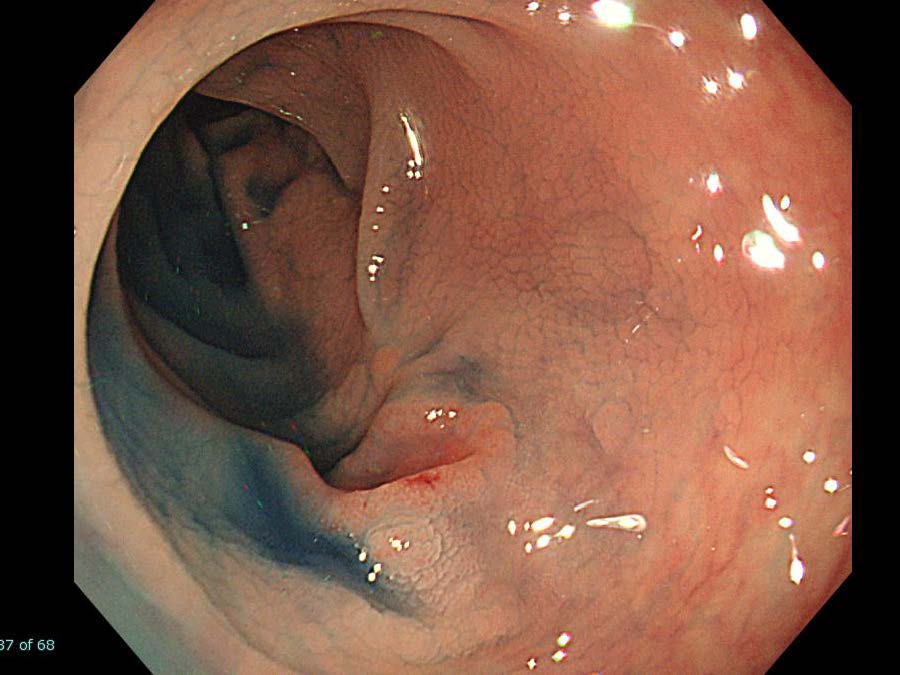

消化管Mapping~大腸~ 2021.10.27

消化管Mapping~大腸~

消化管Mapping